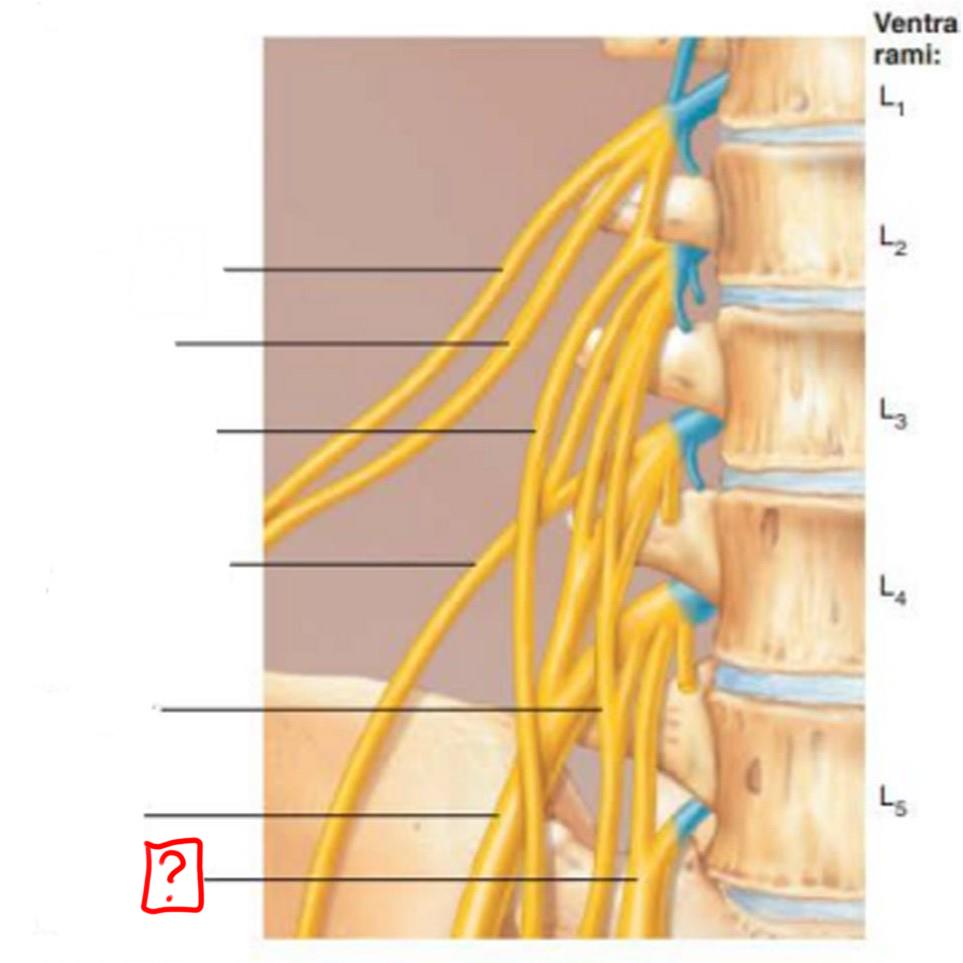

lumbar plexus

L1-L4

major nerves: ilioinguinal, obturator, femoral, genitofemoral

iliohypogastric

ilioinguinal

genitofemoral

lateral femoral cutaneous

obturator

femoral

lumbosacral trunk